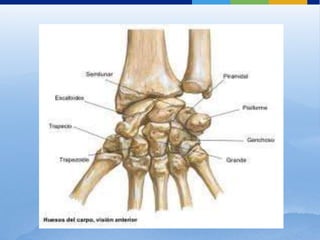

Carpo

Formado por 8 huesos dispuestos en 2 filas:

Escafoides

⬜ El más lateral de la fila proximal

de huesos del carpo

⬜ Tiene un tubérculo en su

superficie palmar

Semilunar

⬜ Mitad de la fila proximal de

huesos del carpo

⬜ Forma de media luna

⬜ Convexidades hacia el radio

Carpo (fila proximal)

Pisiforme

Piramidal

• Lado cubital

• Hueso más pequeño del carpo

• El segundo desde el lado cubital

• Forma piramidal

• Carilla articular en la superficie

palmar

Ganchoso

⬜ Base del pulgar

⬜ Tubérculo y surco: superficie

Trapezoide

⬜ Base del segundo hueso

metacarpiano

⬜ Forma de cuña o triangular

Carpo (fila distal)

Trapecio

Grande

• Medial de la fila distal

• Forma de cuña en la base de los

dedos anular y meñique

• Gancho (apófisis unciforme) en la

• Centro de la fila distal

• Más grande del carpo